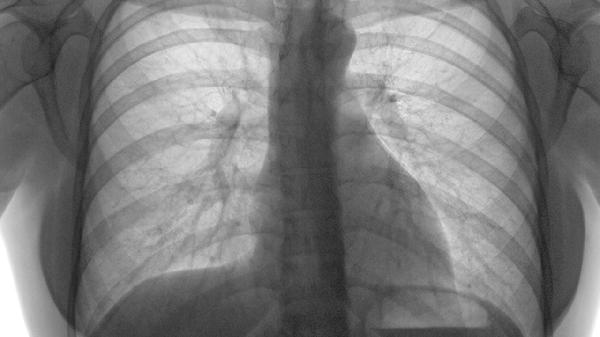

2、CT肺动脉造影:

CT肺动脉造影是目前诊断肺栓塞最准确的方法之一,可以直接显示肺动脉内的血栓位置和范围。这项检查无创且成像清晰,还能评估右心功能和肺部其他病变。但对肾功能不好的患者来说,使用造影剂时要格外小心。